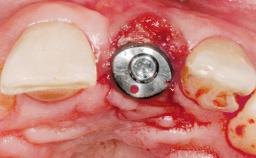

Early Placement of an Implant in a Maxillary Right Central Incisor Site

This 41-year-old female patient was referred to the clinic for the replacement of the right central incisor, since the tooth had developed a root fracture in the long axis that made extraction necessary. The healthy, non-smoking patient was first seen with the tooth still in place. A detailed Esthetic Risk Assessment was performed.The patient was worried about her dental esthetics and had high expectations for a successful treatment outcome from an esthetic point of view. The patient had a medium lip line that displayed parts of the gingiva in the anterior maxilla upon smile.

Type of Implants Two-Piece

Attachment Two-Piece

Bone Volume Deficient horizontally, allowing simultaneous augumentation